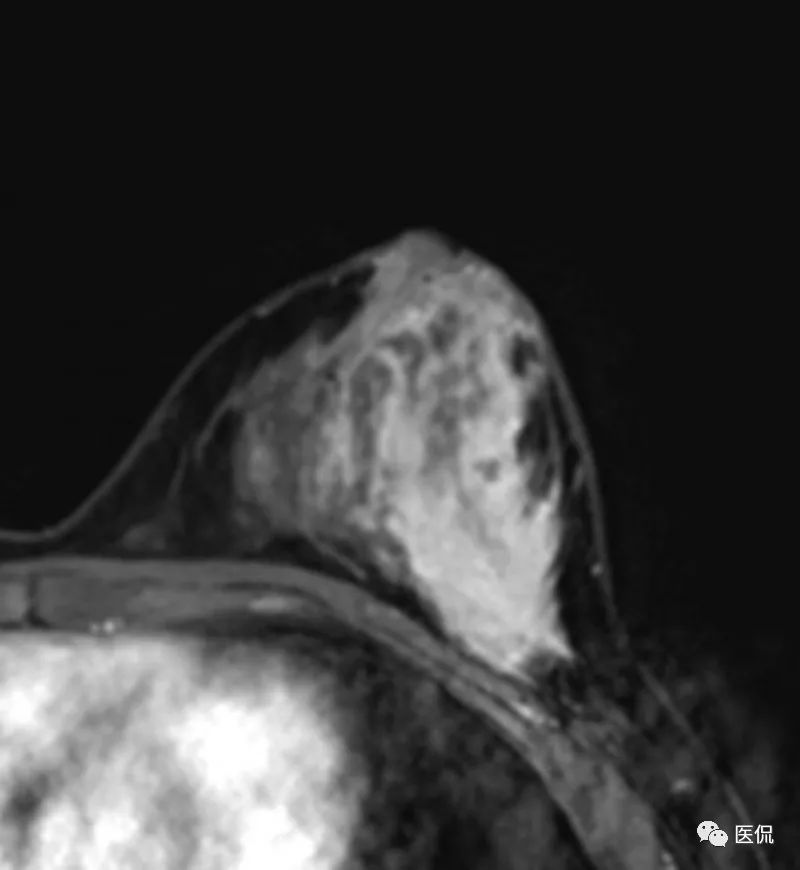

乳腺MRI检查:

MRI检查设备为PHILIPS Achieva 3.0T超导型MRI扫描机,专用乳腺8通道相控阵线圈。患者俯卧位,双乳自然悬垂。先行横轴位梯度回波T1WI序列(TR/ TE=5.15/2.59ms),横轴位快速自旋回波脂肪抑制T2WI序列(TR/ TE=7989.15/70.00ms)平扫,FOV=35cm×16cm,层厚4mm,层间距0.4mm。后行横轴位、矢状位DCE-MRI扫描,采用三维容积梯度回波成像技术脂肪抑制序列(TR/TE=5.4/2.7ms),造影剂用量14ml,速率2ml/s,设定8个时相,无间断扫描,每个时相扫描时间为111s,总动态增强时间约14.8min,FOV=35cm×16cm,层厚4mm,层间距0.4mm。DWI序列,b值0,600。

该例患者有先天性乳头凹陷, MRI图像上,病灶范围较广泛,呈片状,边缘不清,累及乳后间隙,增强后不均质强化,时间信号曲线为平台型,应首先考虑为炎性病变。

本病例特点为年轻女性,以发现左乳肿块1+月就诊,病程较短,有先天性乳头内陷。X钼靶显示左乳外下象限腺体结构紊乱,密度增高,边缘模糊,无钙化,腋窝无增大淋巴结。超声显示病灶范围较为广泛,为混杂低回声区,边缘不清。MRI显示病灶呈片状稍长T2信号,边缘不清,DWI(b=600)为稍高信号,增强后明显不均质强化,时间-信号曲线为平台型。上述影像表现均提示病变范围广泛,边界模糊不清,无肿块显示,结合患者先天性左乳头凹陷,有乳腺炎发病基础,因此在诊断上首先需要考虑浆细胞性乳腺炎的可能性。

乳腺X线摄影是基本检查方法,主要表现为患侧乳腺的大片密度增高,边缘不清,有时可在病灶区域内看到迂曲透亮的扩张导管影。超声可清晰显示扩张的导管,浆细胞性乳腺炎一般分为三型:(1)包块型,肿块多位于乳晕附近,边界不清,形态不规则,与乳腺癌不易鉴别;(2)单纯导管扩张型:乳腺腺体内见多发扩张导管,内透声差;(3)脓肿形成型:范围较广泛,边界模糊,脓肿形成后深压探头可显示脓液流动,光点漂浮。MRI检查具有较好的组织分辨率及空间分辨率,能从多个角度显示病灶的信号、形态特点,T1WI呈等低信号,压脂T2WI呈高信号,动态增强呈不均匀明显强化,脓肿形成后脓肿壁环形强化,DWI脓腔呈明显高信号,时间-信号强度曲线多为I型或II型。对与乳腺癌鉴别具有较大意义。